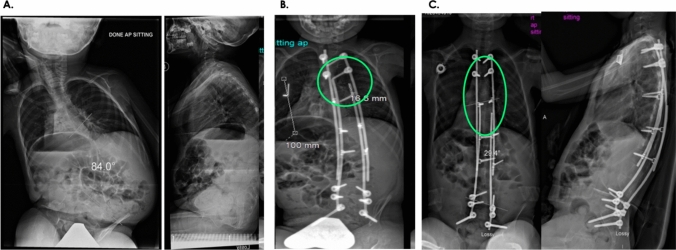

Purpose: Management of early-onset scoliosis (EOS) remains challenging with high reoperation rates. The modern Luque trolley technique (MLT) was developed to reduce open lengthening and complications. This study aimed to compare the reoperation rates between the MLT and other growth-friendly surgical techniques.

Methods: Prospective EOS patients were recruited and treated with MLT; matched historical controls were selected from the Pediatric Spine Study Group (PSSG) database. The primary objective was to test if within 3 years of surgery MLT patients would have fewer reoperations. Secondary outcomes were growth, curve correction, and quality of life using the 24-item early-onset scoliosis questionnaire (EOSQ-24). Safety analysis was performed for the MLT patients.

Results: MLT (N = 18) and control patients (N = 43) had similar baseline age, body measurements, etiology, Cobb angle, and spinal length. Within 3 years of surgery, 1/18 MLT patients required a reoperation compared with 30/43 controls, conditional Poisson regression rate ratio = 0.02 (95% CI 0; 0.12) (P < 0.001). The median time to first reoperation was MLT, 5.4 years and control, 0.8 years. The MLT achieved the same curve correction as the controls at 3 years. The total spinal growth (T1-S1) was similar between the groups, although the thoracic spinal growth (T1-T12) was less in the MLT group. No difference was observed in standing heights and EOSQ-24 scores. Within 3 years, 2 MLT patients had recurrence of deformity (risk = 11.1%, 95% CI 1.4; 34.7) and 1 had implant loosening (risk = 5.6%, 95% CI 0.1; 27.3).

Conclusion: MLT patients had fewer reoperations within 3 years than control patients and a low risk of implant failure.